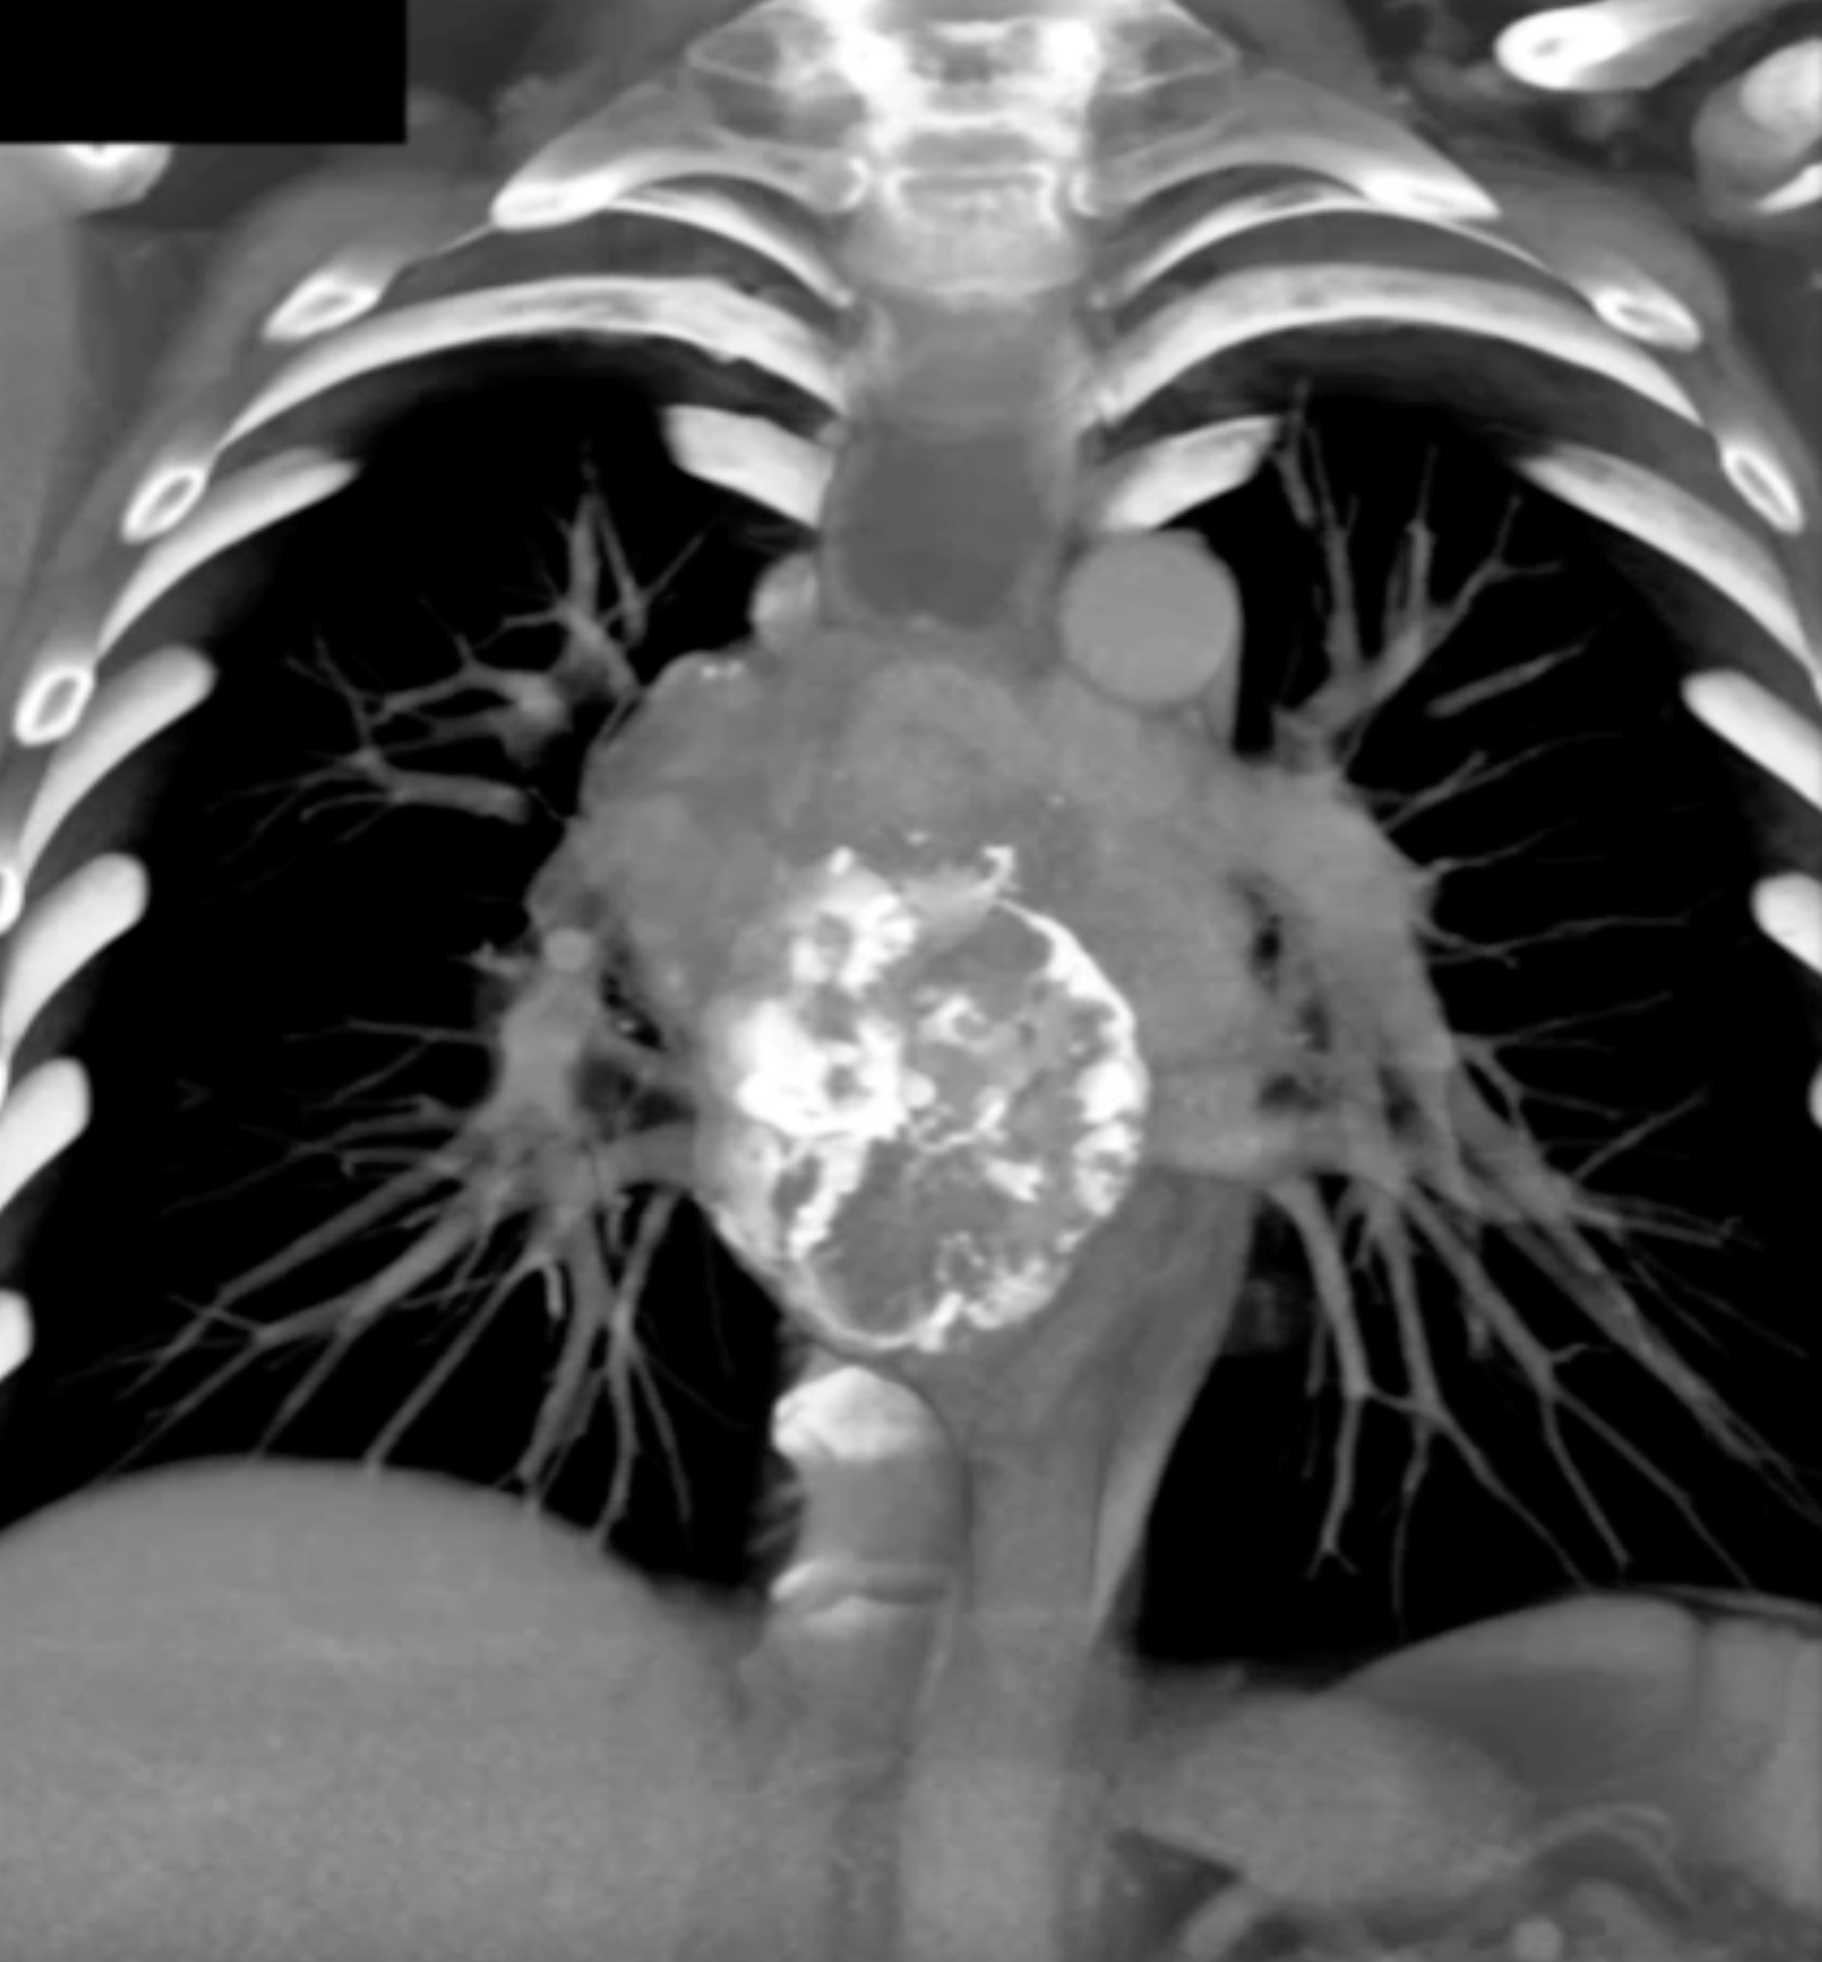

Fibrosing Mediastinitis